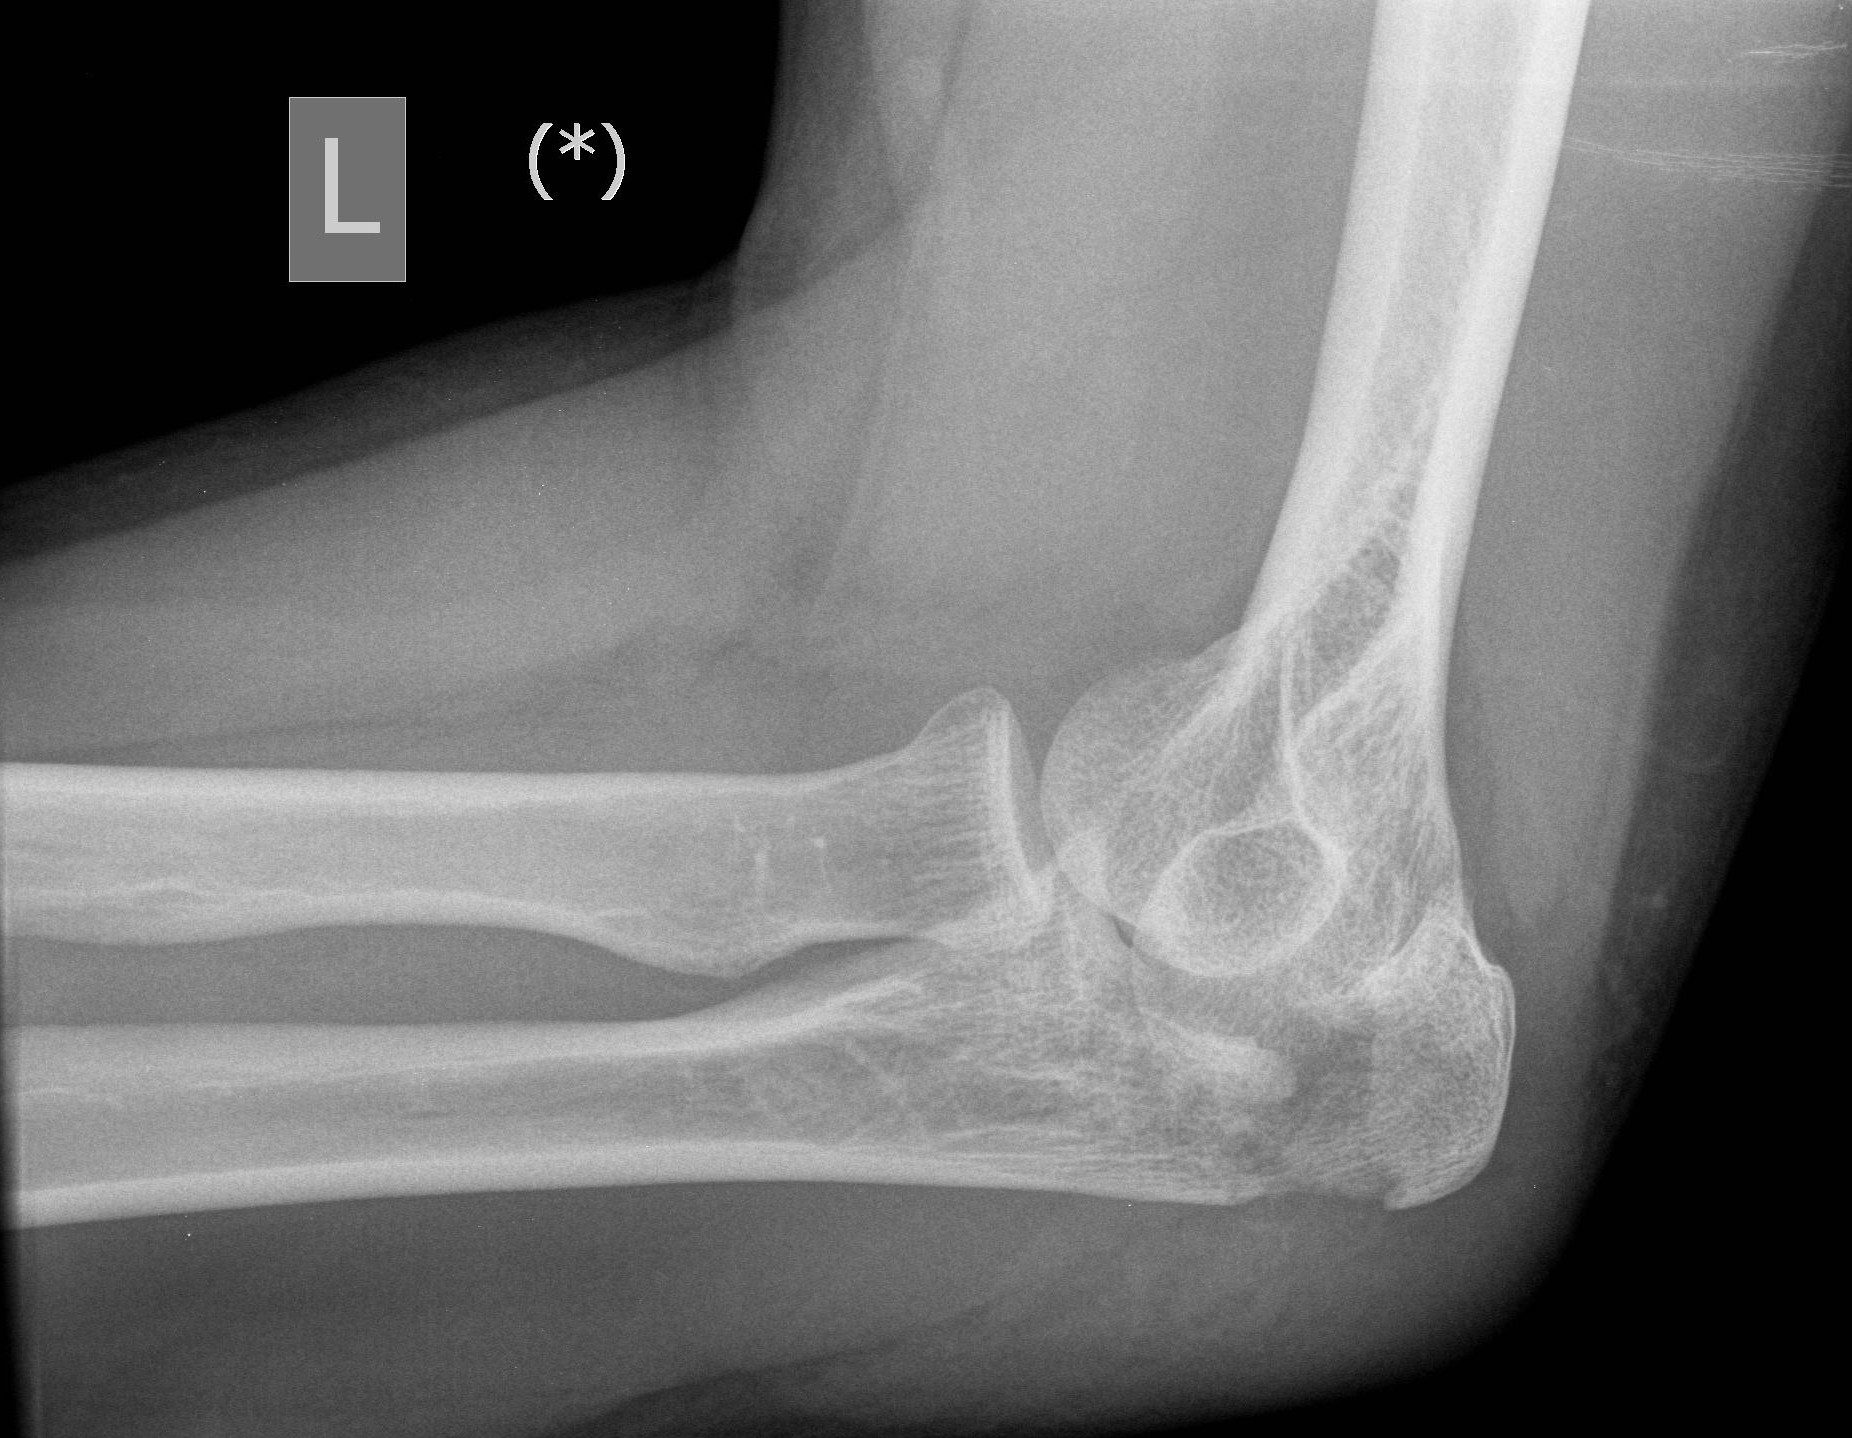

From radiopaedia.org

Pediatric olecranon fracture subtle Image Olecranon Fracture Cast Position Along with the coronoid process, it forms the greater sigmoid. Surgical and nonoperative management of olecranon fractures in the elderly: Diagnosis can be made with plain radiographs of the elbow. This pointy segment of bone is part of the ulna, one of the three bones that come. Occurs via direct trauma or by fall with forced hyperextension of elbow. Common. Olecranon Fracture Cast Position.

Olecranon Fracture Cast Position . Along with the coronoid process, it forms the greater sigmoid. This pointy segment of bone is part of the ulna, one of the three bones that come together to form the. This pointy segment of bone is part of the ulna, one of the three bones that come. The olecranon is the proximal articular portion of the ulna. Common in high energy mechanism in young and falls in elderly. Surgical and nonoperative management of olecranon fractures in the elderly: Diagnosis can be made with plain radiographs of the elbow. Occurs via direct trauma or by fall with forced hyperextension of elbow. Olecranon fractures are common fractures of the elbow that lead to loss of extensor mechanism.